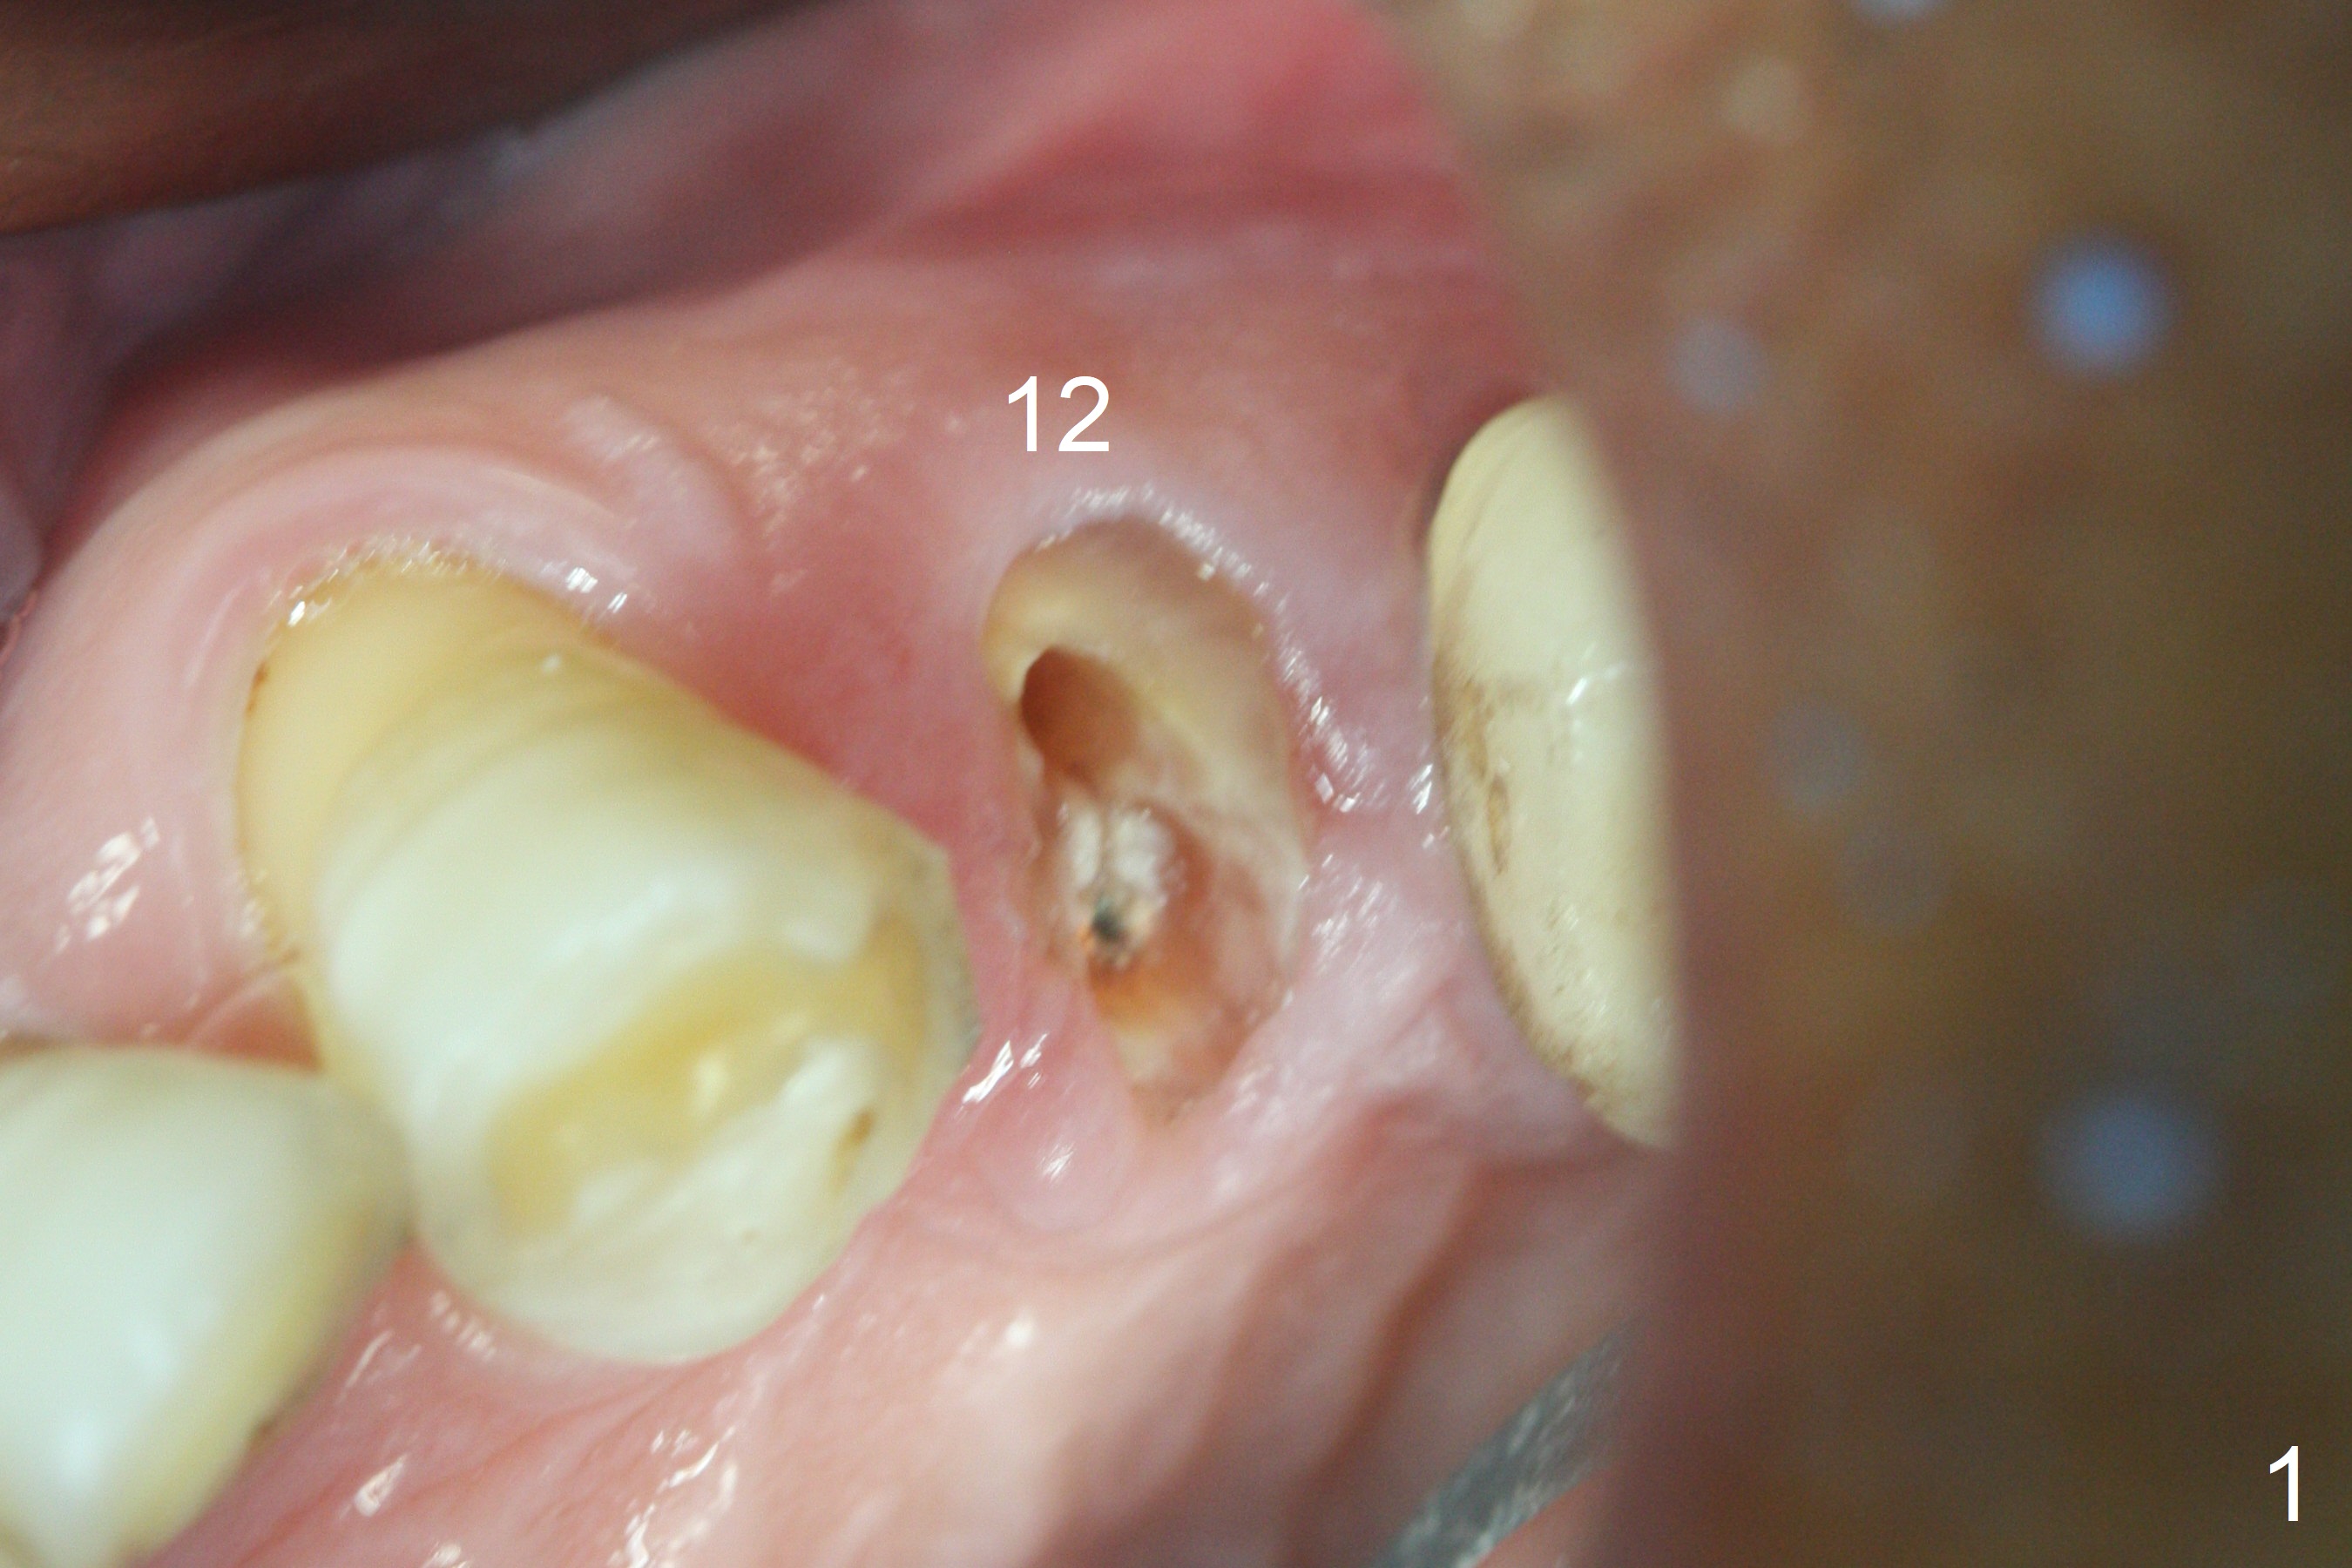

After extraction of the oval-shaped residual roots at #12 (Fig.1), osteotomy is initiated in the palatal socket for 18 mm; since the root of the canine curves distal (Fig.2 red dashed line), the osteotomy cannot afford to move mesial and extend more apical.  A 3.8x15 mm implant is placed with > 50 Ncm (Fig.3).  With immediate placement of a 4.5x4(3) mm abutment, an immediate provisional is fabricated to close the sockets (Fig.4 P).  The provisional has clearance from the RPD clasps (Fig.5).  In fact the implant could be longer, as shown by immediately postop panoramic X-ray (Fig.6).  The implant seems to be osteointegrated 3 months postop (Fig.7).  The tooth #13 is symptomatic with caries (Fig.8 C) 7 months post #12 crown cementation; the #13-15 FPD dislodges.  The upper left quadrant is cold and hot sensitive 2.5 months post RCT (Fig.9); although there is mild percussion at #13, pulpal test shows that the tooth #15 has lingering pain.  The FPD was recemented temporarily after RCT; it cannot be removed.  The implant crown has been loose for several months during the pandemic before he returns 2 years 7 months post cementation.  In fact the abutment has been not seated completely (from Fig.3 to 9).  The crown/abutment is removed from the mouth; the crown is sectioned and separated from the abutment; the latter is reseated, but incompletely (Fig.10 <).  With suspicion of the mesial crestal contact, profile drills 4.6 and 5.5 mm are used without effect.  A new (old probably being worn) and longer (easy to turn in the narrow space) abutment is finally seated completely (Fig.11 (no gap)).  After occlusal adjustment, abutment level impression is taken for a new crown.